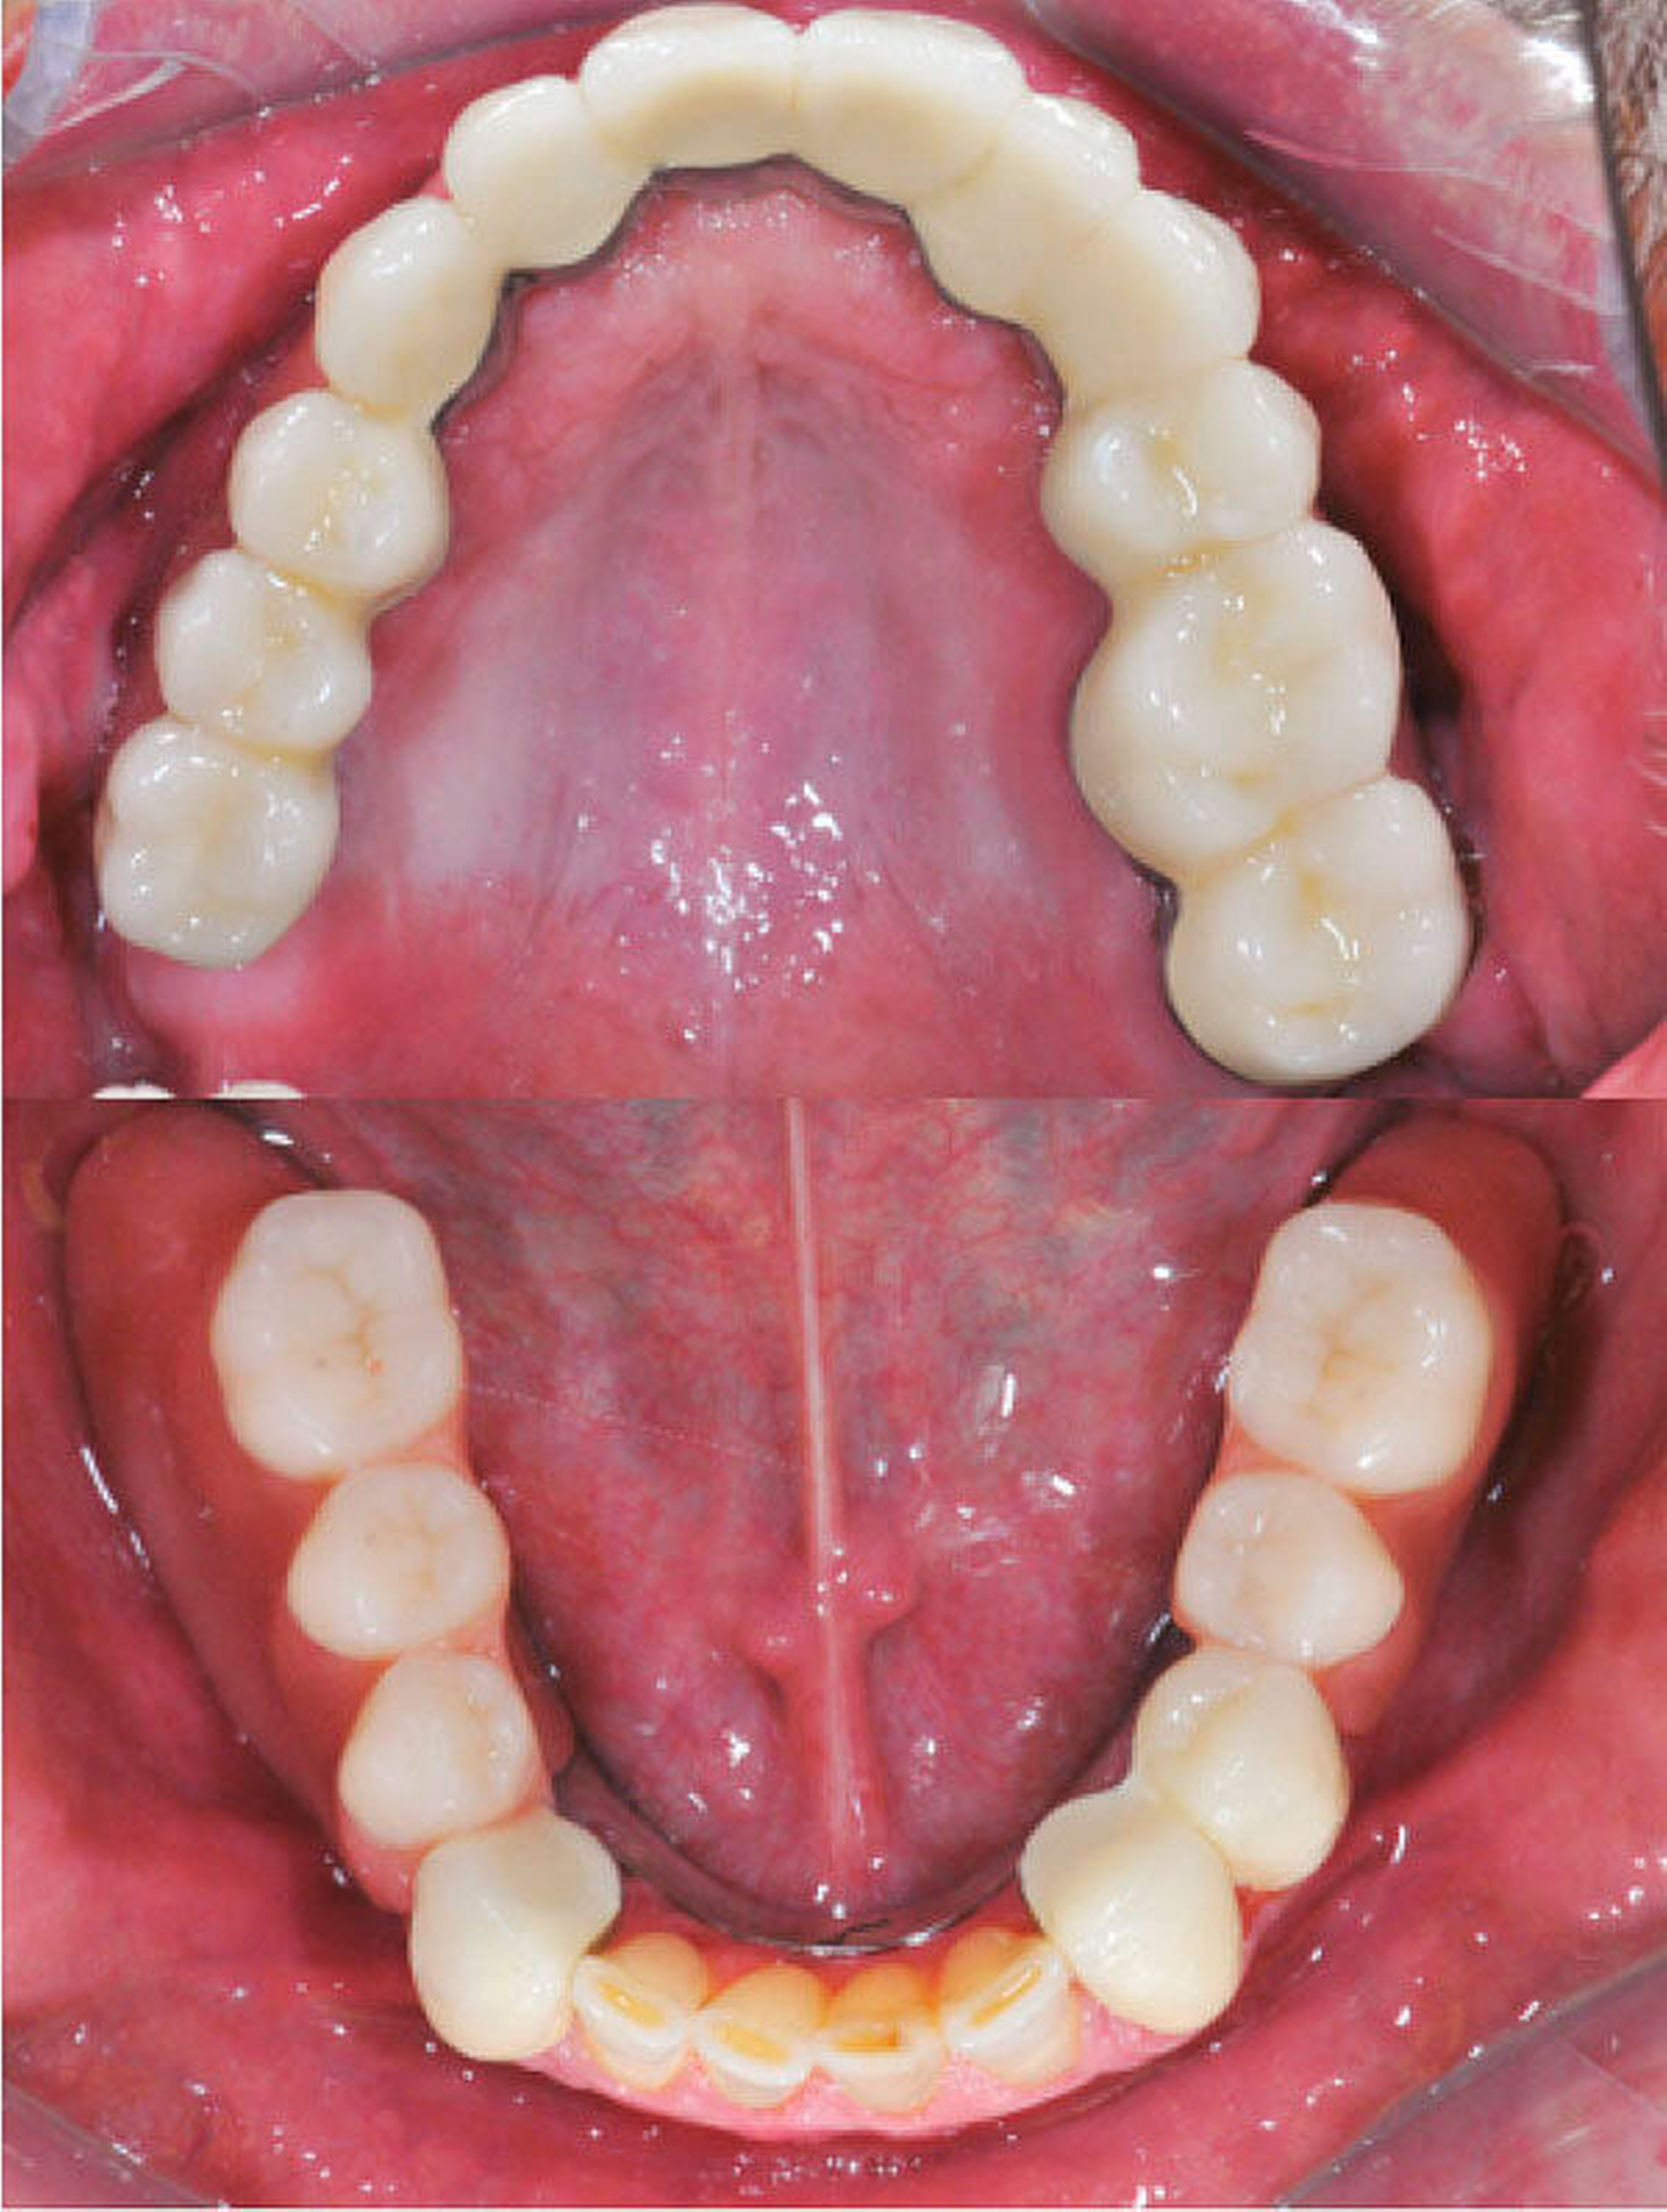

Nach unauffälliger Heilung ohne Komplikationen und Korrektur der Kieferrelation (Abbildung 5) konnte die definitive Versorgung (CARES®; Straumann, Basel, Schweiz; Sinfony®, 3M ESPE, Seefeld, Deutschland) drei Monate später eingegliedert werden (Abbildung 6). Im Rahmen der Nachsorgeuntersuchungen (Follow-up aktuell: 2,5 Jahre) zeigten sich stabile Okklusionsverhältnisse bei reizlosem Lokalbefund.